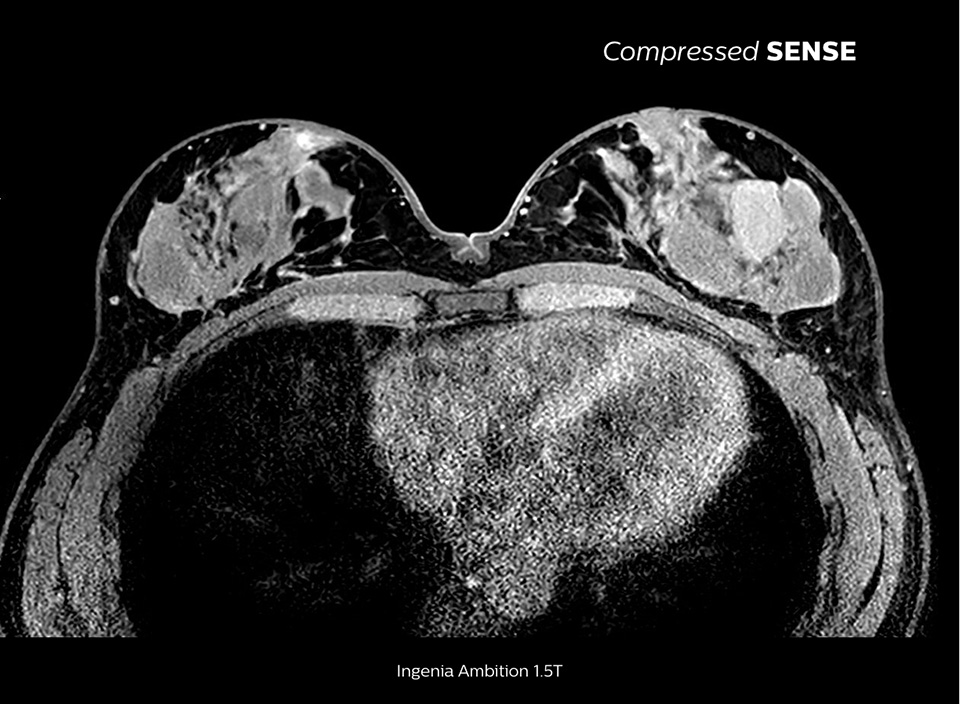

画質の劣化を伴うことなく、3Dシーケンスを最大50%高速化1

倉敷中央病院における高品質で高速なスキャン

倉敷中央病院のMRIスタッフは、Ingenia 1.5Tを使用した検査プロトコルのうち、脳、脊椎、腹部、心臓領域を対象とした検査の大部分にCompressed SENSEを使用しています。その結果、高速かつ高品質のMRIスキャンを実現し、患者やスタッフからも高い評価を受けています。

Compressed SENSEを選択するその他の理由

MR検査が最大50%高速化

高空間分解能化による画質改善